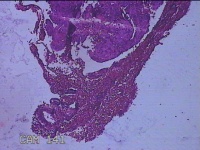

宫颈管内组织

性别

女

年龄

46岁

临床诊断

异常子宫出血

一般病史

阴道流血伴血块6天。

标本名称

大体所见

灰白暗红色不规则碎组织1.5x1.3x0.3cm一堆。

图2